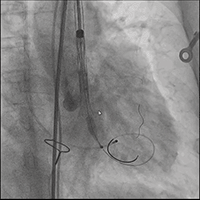

行左冠保护,预置左冠球囊

● 第一次释放,初步张开后给予160次/分起搏,起搏后血压未降低反而升高至约135/80mmHg,释放前1/3过程中发生上跳,故回收。

● 第二次释放,初始定位在瓣下4mm,瓣膜张开后起搏,血压仍不降反升,仍在前1/3释放中发生上跳,故回收。

● 第三次释放,定位瓣下4mm再次尝试,起搏后释放,仍有上跳趋势,故回收。

● 第四次释放,定位约瓣下8mm,瓣膜初始张开后,略提拉寻找锚定位置,至瓣下4mm位置,起搏准备释放至工作位,仍有上跳趋势,故回收,考虑到远期患者获益,更换新瓣膜尝试。